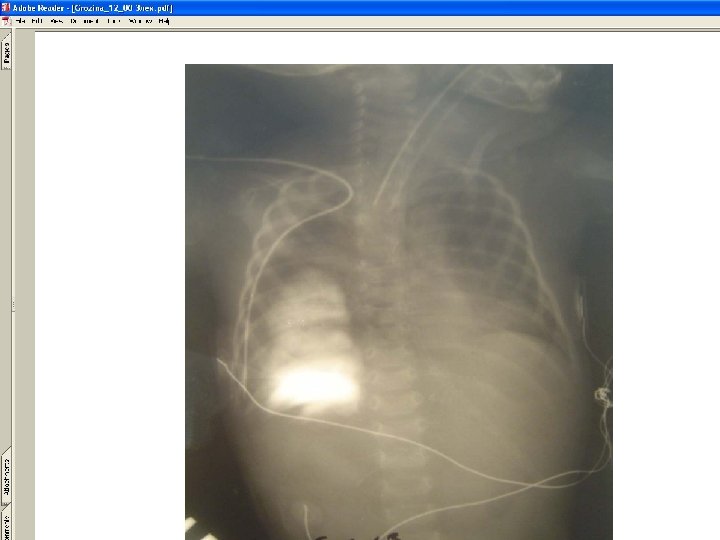

• Types of catheter malposition